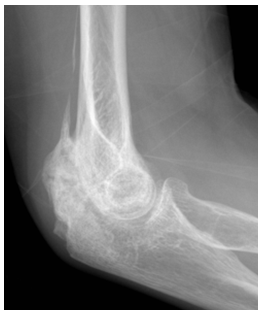

X-ray: 뼈의 상태와 관절의 정렬 상태를 평가하며, 골절이나 관절염과 같은 다른 원인을 배제합니다.